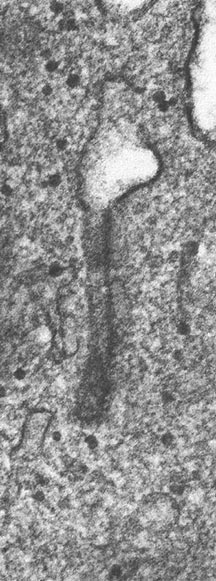

- Birbeck Granules: Electron Microscopy demonstrates granules that often take the form of a tennis raquet and form from complex invaginations of the cell membrane